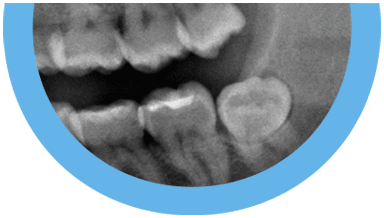

Plano de tratamento: Colocação de 4 implantes superiores e 2 implantes inferiores. Confeção de uma barra superior e colocação de 2 locators® na parte inferior. Confeção de uma prótese superior e outra inferior removível, com encaixes na barra e locators®.